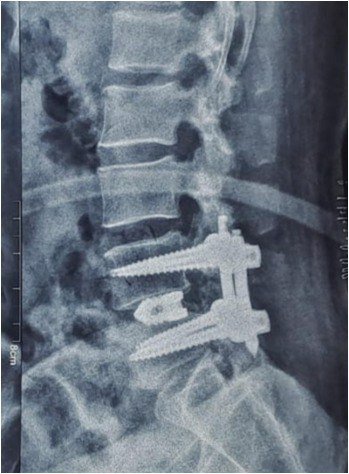

Interventional & Surgical Options

Reserved for persistent symptoms or instability.

- Spinal stabilization if associated with slip